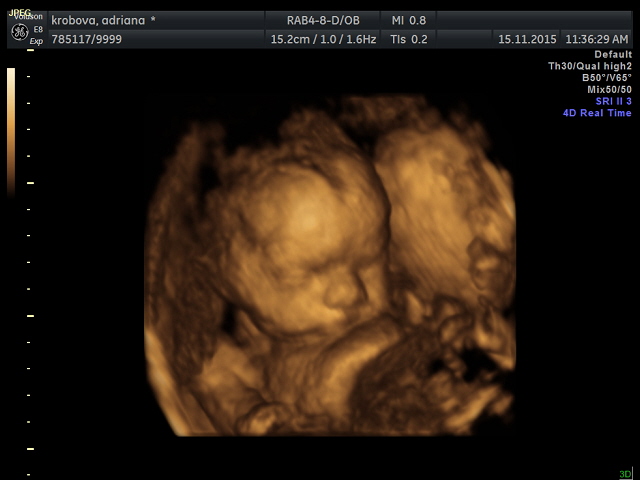

Krásná fotečka miminečka

Hani máš krásnou fotečku :-) Teda. Holky do kdy je vidět mimčo tak nějak, aby udělali obrázek? Já jdu v pondělí a budu už 29+1, myslíte, že by nám udělala ještě obrázek? Chci ji narovinu říct, že když to půjde tak chci něco hezkýho a ne to co nám dala minule, kde není vůbec vidět.

Eli, nas stala svatba pro 35 lidi vcetne ubytovani asi poloviny, ktera chtela, a jidla i druhy den rano... asi 35 tisic. Vsichni jsme byli spokojeni... Tobe preju uzasnou svatbu a same krasne zazitky, bez ohledu na to, co kolik stalo. Budes krasna nevesta i s temi kily navic :-* ..... Manzel me chtel taky vic fotit, ne teda nic nechutnyho, ale nakonec mame jen par fotek po narozeni maleho, protoze mel se mnou a vsim okolo plne ruce prace. Jesteze tam byl. ....... Hani, to je asi nejhezci 3D fotka, co jsem videla. ...... Janci, micham si vlastni bylinky nebo mnou alespon nasbirane - skoro vzdy dam slez maursky, yzop (toho jen trochu), kvet bezu, lipy, no a k tomu obcas sipek, jitrocel, materidousku, fenykl, malinko salveje, mesicek... Proste co me zrovna napadne. Tomik to zvladne vypit i bez medu :-), Tobi spis s medem. Jinak piju Vincentku a tu nam i strikam do nosu. Kdyz citim dutiny, udelam si salvej a tu si dam do nosu taky, nebo inhaluju horkou paru treba s tea tree oilem. Ten taky kloktam, kdyz me boli v krku a nejsem lina... Nebo kloktam propolis. Variant je hodne. Ale ted jsem si dala na noc i Paralen.

Takže miminko 8 je Matěj schovaný za ručičkou- kde vykukuje jen nosánek, pusinka a trochu stín oka :0) Líp ho Rozárka nenechala "cvaknout" No a třináctka je naše modelka :0))